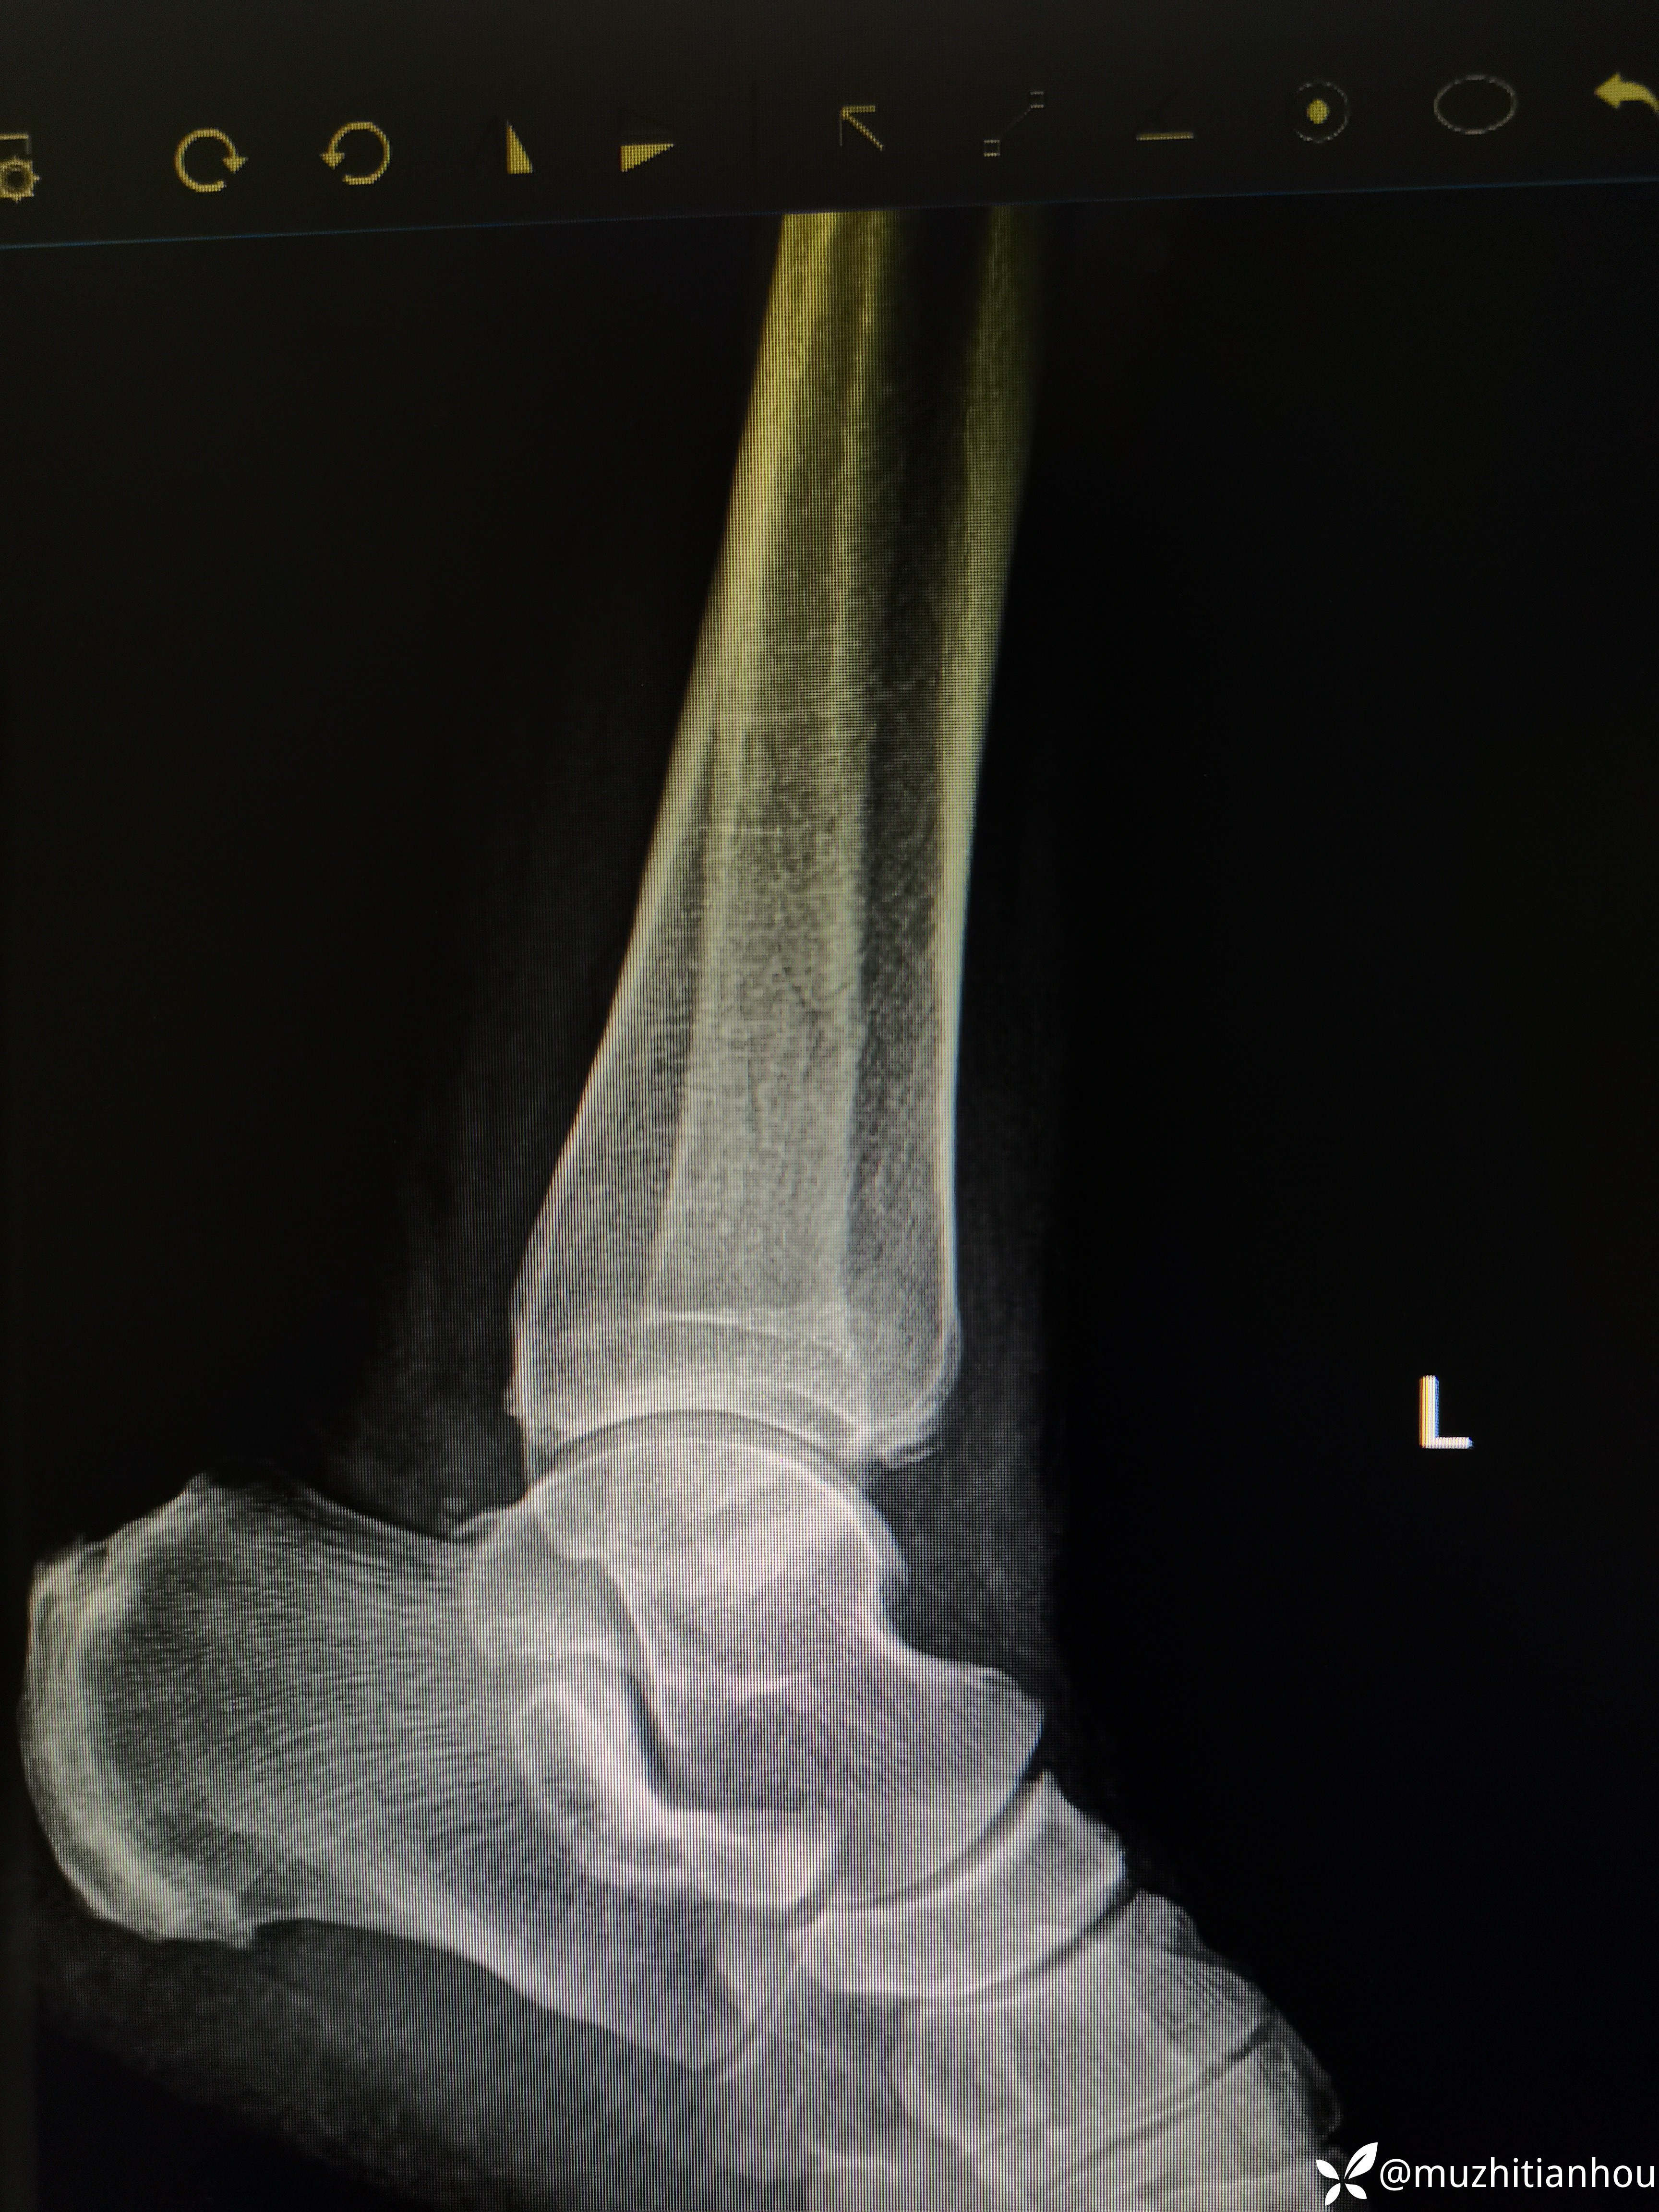

返回头来我们再阅片发现正位下胫腓存在骨块,存在分离移位,内踝侧位片骨折线前上后下亦存在分离移位,虽然腓骨长度没问题,但凭借这两处骨折和四度损伤样也完全说明手术指征明确。

侧位没经验的大夫会不会看内踝呢?有什么端倪吗?门诊碰到这样的患者问你能不能保守治疗,你会怎么处理?

内踝看到了移位,没有想象的那么好。